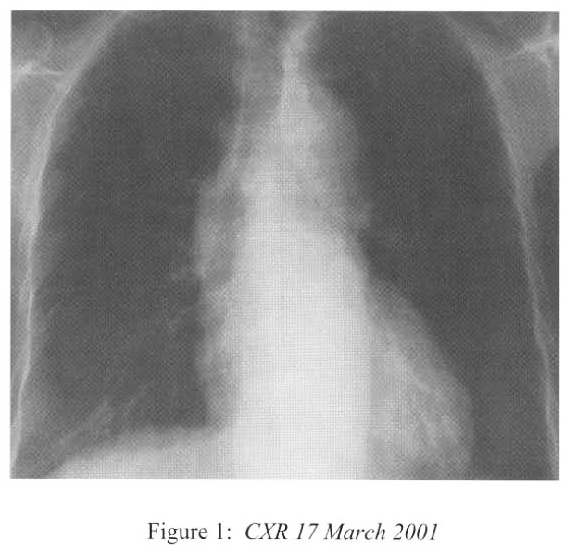

One day later she became hypotensive. There has been no change in her steroid doses and she remained afebrile. Peritoneal dialysis was withheld and intravenous fluid replaced. She passed tarry stool and this was supported with transfusion. The hypotension persisted and she eventually required inotropes infusion (dopamine and dobutamine) for blood pressure support. Her general state deteriorated with lethargy, vomiting and anorexia. She was further supported with parenteral nutritional. Dyspnoea recurred during this period of time. CXR showed diffuse bronchopneumonia in addition to the persistent right lower zone consolidation. (Figure 2) The creatinine level rose up to 912 umol/L.

Radiological features are also diverse and variable 15,16.On the chest radiograph, early signs include miliary shadows, diffuse reticular interstitial opacities, patchy alveolar opacities, segmental or lobar opacities. In the advanced stage, there can be extensive airspace shadows affecting both lungs, with occasional pleural or pericardial effusion. Without treatment, ARDS quickly evolves. Rarely, ARDS develops after antihelminthic treatment due to release of toxic breakdown products 17.On the abdominal radiograph, there can be thickened mucosal folds, segmental small bowel dilatation or perforation. Among all these variable radiological features, a characteristic pattern of Strongyloides hyperinfection has been described by the radiologists of Hong Kong, which consist of fleeting and rapidly changing CXR signs, predominant small bowel abnormality on AXR, and close temporal relationship of CXR & AXR signsl8. Detection of larvae in stool or other specimens is difficult (Table 1). Serological diagnosis19 is an attractive alternative but it is not available in Hong Kong.